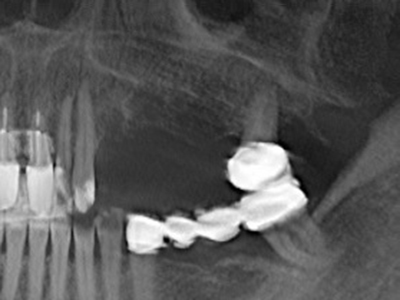

Piezosurgery has additional advantages when harvesting bone blocks. In addition to the high precision with osteotomy described above, the use of the thin saw tips specifically minimizes loss of material. Greater loss of material during harvesting can be expected with the thicker instrument tips, particularly when using Lindemann drills (Lakshmiganthan, Gokulanathan et al. 2012). The basal separation, which is necessary particularly for retromolar block transplants, is simplified by specially designed rectangular saws, with the result that piezosurgery is viewed as a precise, simple and safe procedure for harvesting retromolar bone blocks (Happe 2007) (Fig. 1-12).

When surgical procedures are performed on bone in the immediate vicinity of sensitive structures such as blood vessels or nerves, rotary instruments pose a significant risk of iatrogenic injury. Piezoelectric devices can be helpful for preparation of bone covers and removal of hard tissue close to nerves, particularly for exposure of nerves after iatrogenic injury but also during nerve lateralization for resective and reconstructive procedures or implant placement (Fig. 17-20). Light contact between the piezotip and the nerve does not generally result in damage but proceeding incautiously with saw-like motions or attachments where a residual bone substrate remains may cause temporary or even permanent nerve damage. However, the risk of damage is considered to be substantially lower than when using saws or milling instruments (Pereira, Gealh et al. 2014).